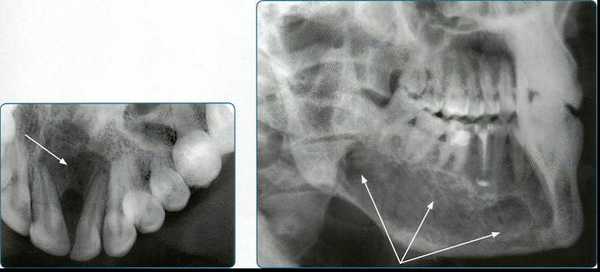

Гемангиома челюсти сравнительно редко бывает изолированной и в большинстве случаев сочетается с гемангиомой мягких тканей лица и полости рта. Сосудистые опухоли челюстей проявляются повышенной кровоточивостью десен, кровотечениями из корневых каналов при лечении пульпита или периодонтита, из лунки при удалении зуба и пр. При осмотре может выявляться флюктуация, расшатанность зубов, синюшность слизистой оболочки.

Для контрастирования артериальных и венозных сосудов челюстно-лицевой области (при образованиях, гемангиомах) контрастный препарат можно вводить тремя способами. Наиболее простым из них является пункция гемангиомы с введением контрастного вещества в толщу опухоли и регистрацией изображения на отдельных снимках. Чтобы получить представление о распространенности опухоли в прямой и боковой проекциях, пункцию выполняют 2 раза. Методика обеспечивает выявление характера венозных изменений, но не всегда позволяет увидеть детали кровотока, подходящие к гемангиоме сосуды, и не пригодна для контрастирования артериальной сосудистой сети.

При кавернозных гемангиомах и артериовенозных шунтах практикуют введение контрастных препаратов в приводящий сосуд, который выделяют операционным путем.

При пульсирующих артериальных и артериовенозных образованиях производят серийную ангиографию после введения контрастных препаратов в приводящий сосуд.